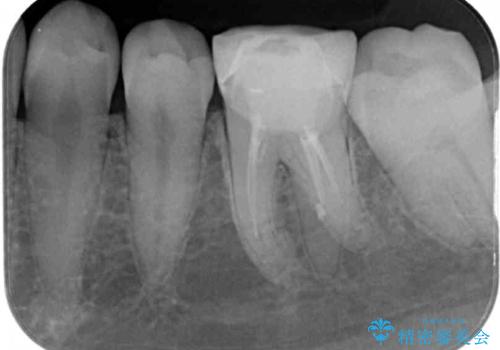

- 奥歯の形が気に入らないとのことで来院された患者様です。

形の変更を希望して、即日装着可能な歯科医院にて治療をしたそうですが、思い通りの形にできなかったとのことでした。

修正可能なように、従来通り技工所に発注して製作するオールセラミッククラウンにて補綴することとしました。